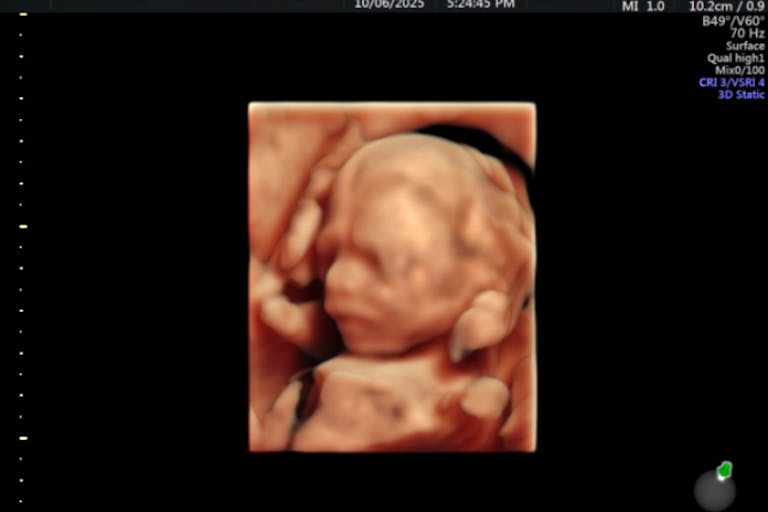

Have you ever wanted to share the miracle of human development with little ones? Live Action is proud to present the "Baby Olivia" board book, which presents the content of Live Action's "Baby Olivia" fetal development video in a fun, new format. It's perfect for helping little minds understand the complex and beautiful process of human development in the womb.